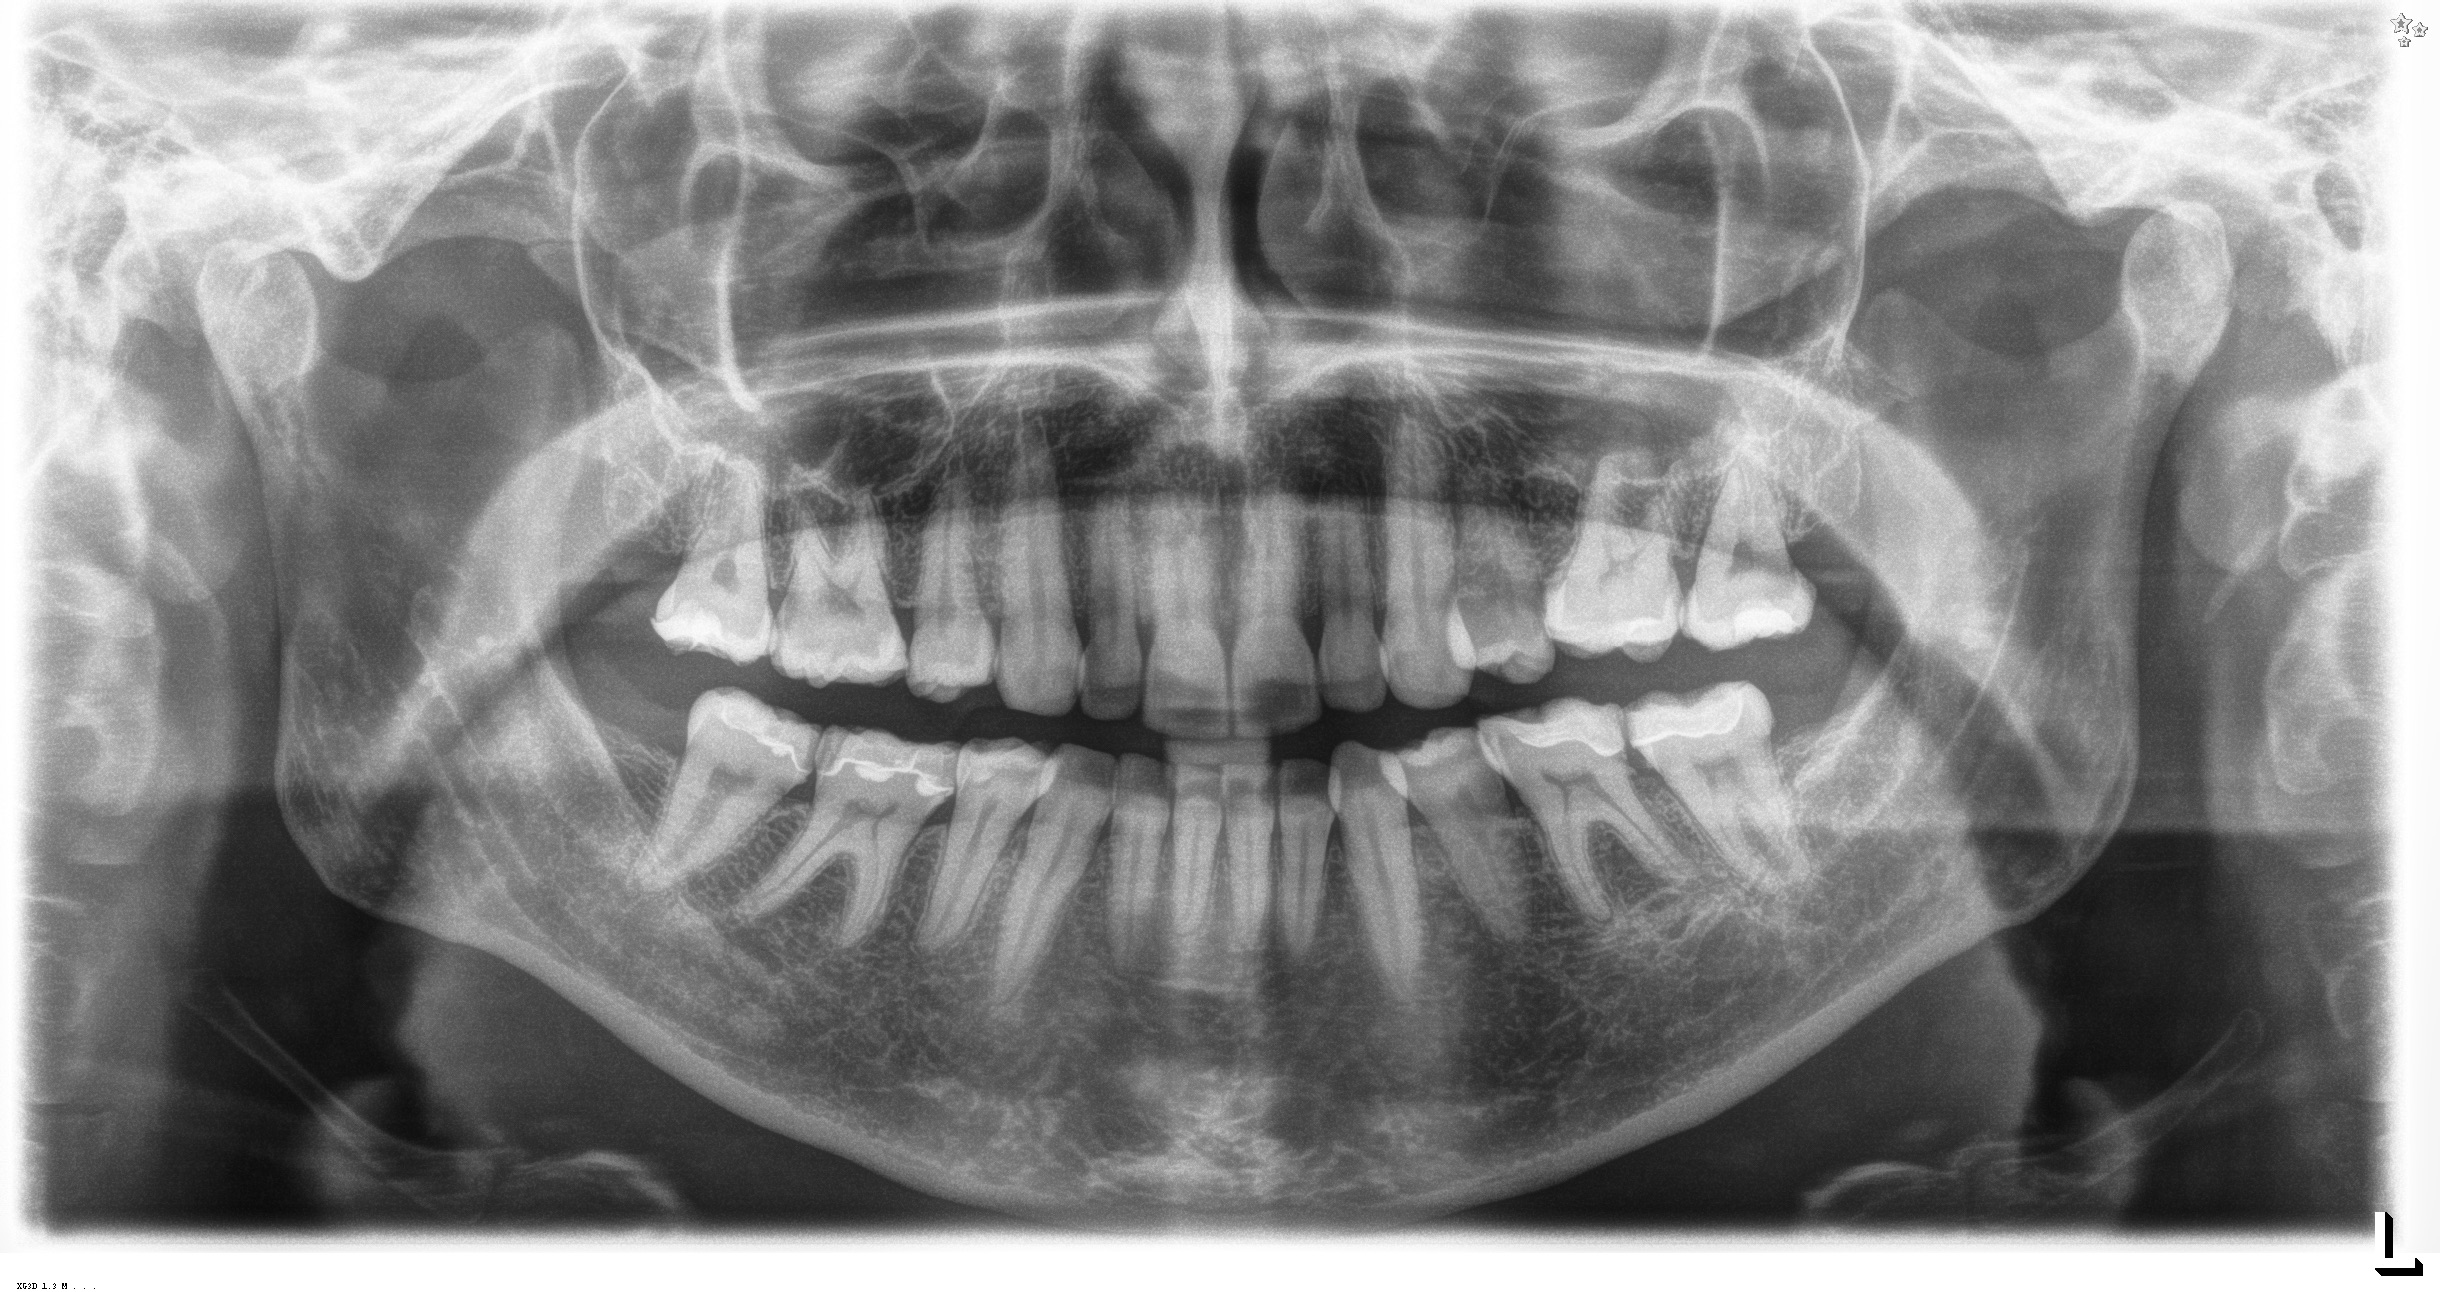

R_F_20141212_2200

2440 × 1292

Z.n. Schmerzbehandlung am Zahn 27